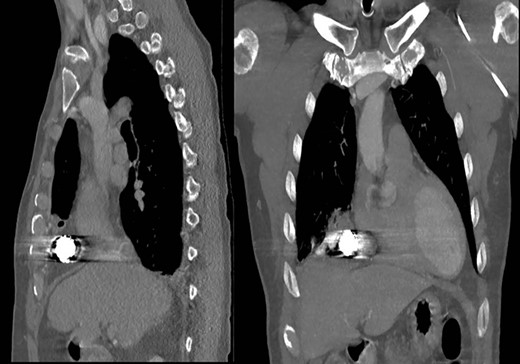

Operative image of the removed intrathoracic bean bag with intact Kevlar coating.

Subsequent review of bean bag projectiles and discussion with the law enforcement officers monitoring the patient revealed that the bean bag projectile included nonmetal components. Out of concern for infection risk, the surgical team performed video-assisted thoracoscopic surgery (VATS) on hospital Day 3 whereby the projectile was successfully removed (Fig. 3). Upon intra-operative inspection, the right middle lobe was contused but not actively bleeding, so no further intervention was performed, and a new chest tube was placed. On post-operative day (POD) 3, the chest tube was removed; however, on POD 6 purulent drainage was observed from the previous bean bag entry wound, and laboratory evaluation revealed a leukocytosis to 21.0 K/mm3. The clinicians irrigated the wound at the bedside and initiated antibiotics treatment. Due to persistent leukocytosis and drainage of purulent fluid from the wound, the clinicians obtained a CT scan on POD 7, which showed a complex right pleural effusion that communicated with a small pocket of fluid in the chest wall, concerning for an empyema (Fig. 4). The following day, the surgeons performed VATS decortication, removing a significant amount of purulent pleural fluid and fibrinous exudate and placing two chest tubes. Culture of the pleural fluid grew Staphylococcus aureus. By POD 11/3, the patient had a persistent right-sided effusion, which the team treated with intrapleural tPA/Dornase infused via previously placed chest tubes. By POD 20/12, the patient’s leukocytosis and right-sided effusion had resolved, and both chest tubes were removed. He was discharged the subsequent day and has not returned to our facility since then.